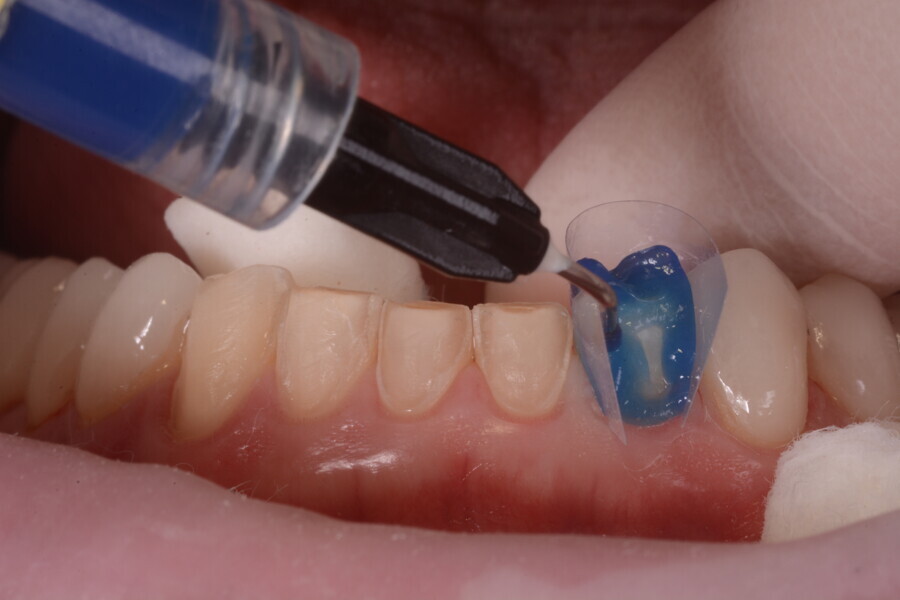

Fig. 8: No preparation of the posterior teeth and minimal preparation of the mandibular anterior teeth. Teeth #11–13 and 21–23 had already been prepared.